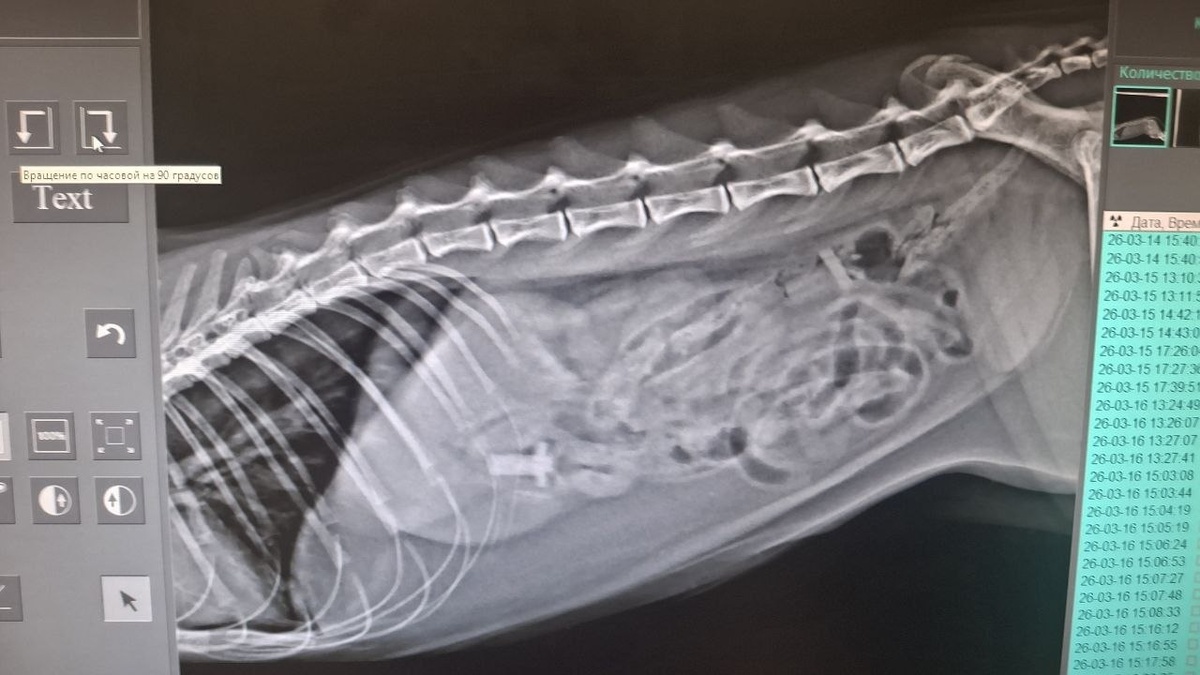

Позвонила клиентка, кота рвёт. Плохо ест, но воду пьет, бодр и весел. До этого играл с пульками от игрушечного пистолета. Пульки нашли на рентгене. Проблема не только в пластиковой части, а ещё и в пороллоновом «хвосте», который не даёт этой пульке продвигаться по кишечнику. Обошлись малой кровью (но приличной ценой). Достали в клинике пульки эндоскопом. Без разрезов. Одну через «вход», вторую через «выход».

Пульки нашли на рентгене. Проблема не только в пластиковой части, а ещё и в пороллоновом «хвосте», который не даёт этой пульке продвигаться по кишечнику.